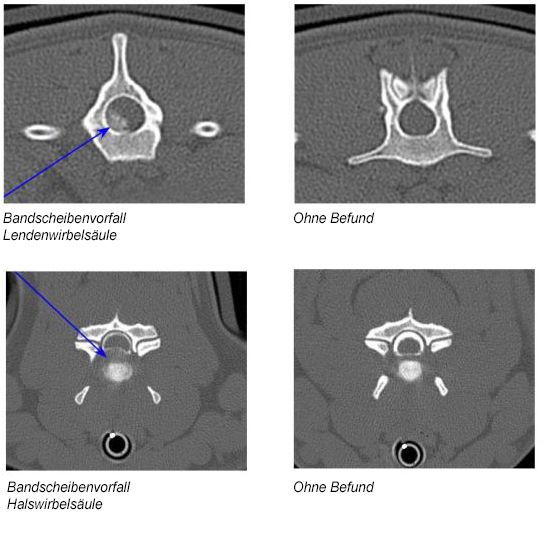

In manchen Fällen sind weiterführende Untersuchungen notwendig, wie zum Beispiel die Punktion von Liquor (Gehirnwasser), eine computertomographische oder eine magnetresonanztomographische Untersuchung, die in Narkose durchgeführt werden müssen.